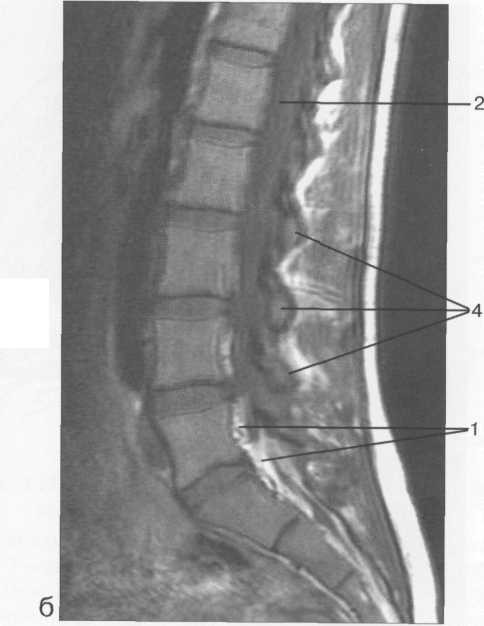

МРТ исследования дают широкую возможность исследовать  все структуры спинного мозга в разных плоскостях. ( рис. 37-41 )

Рис. 37. Срединные сагиттальные МРТ пояснично-крестцового отдела позвоночника.

а-Т2-ВИ;б-Т1-ВИ.

1 -- конус спинного мозга; 2 -- конский хвост спинного мозга; 3 -- субарахноидальное пространство; 4 -- дуральный мешок; 5 -- терминальная нить; 6 -- эпидуральное пространство; 7 -- тело Sp 8 -- пуль­позное ядро межпозвонкового диска; 9 -- фиброзное кольцо межпозвонкового диска; 10 -- каналы бази-вертебральных вен; 11 -- остистый отросток LIV.

Рис. 39. МРТ. Парасагиттальное изображение пояснично-крестцового отдела позвоночника.

-- эпидуральное пространство; 2 -- субарахно-идальное пространство; 3 -- корешки спинно­мозговых нервов; 4 -- пластины дуг позвонков.